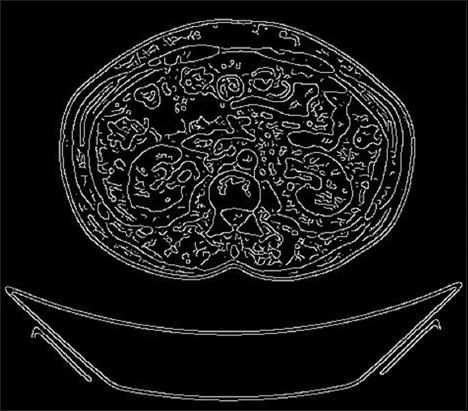

Following the pre-processing stage, the segmentation phase was executed to identify objects and boundaries within the images. The outcome of this segmentation process is depicted in Fig. 4.

thumblarge

Fig. 4. Segmented image.

After applying Canny edge detection to segment a kidney CT image, the resulting image clearly defines and outlines the kidney structure. This high-contrast image significantly aids in the accurate identification of kidney stones.